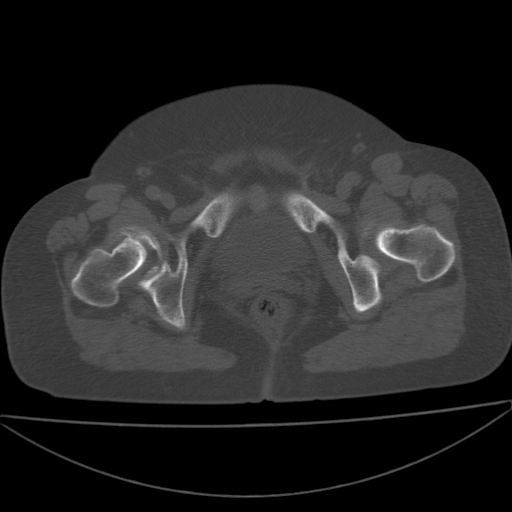

以下是引用余辉在2009-4-23 17:08:00的发言:[br]考虑右髋关节退行性变.股骨颈改变考虑陈旧性骨折可能,股骨头顶部关节面下似有透亮区,股骨头皮质环增厚,考虑有股骨头坏死

以下是引用王显瑞在2009-4-23 16:45:00的发言:[br]考虑股骨颈陈旧性骨折,股骨头缺血型坏死